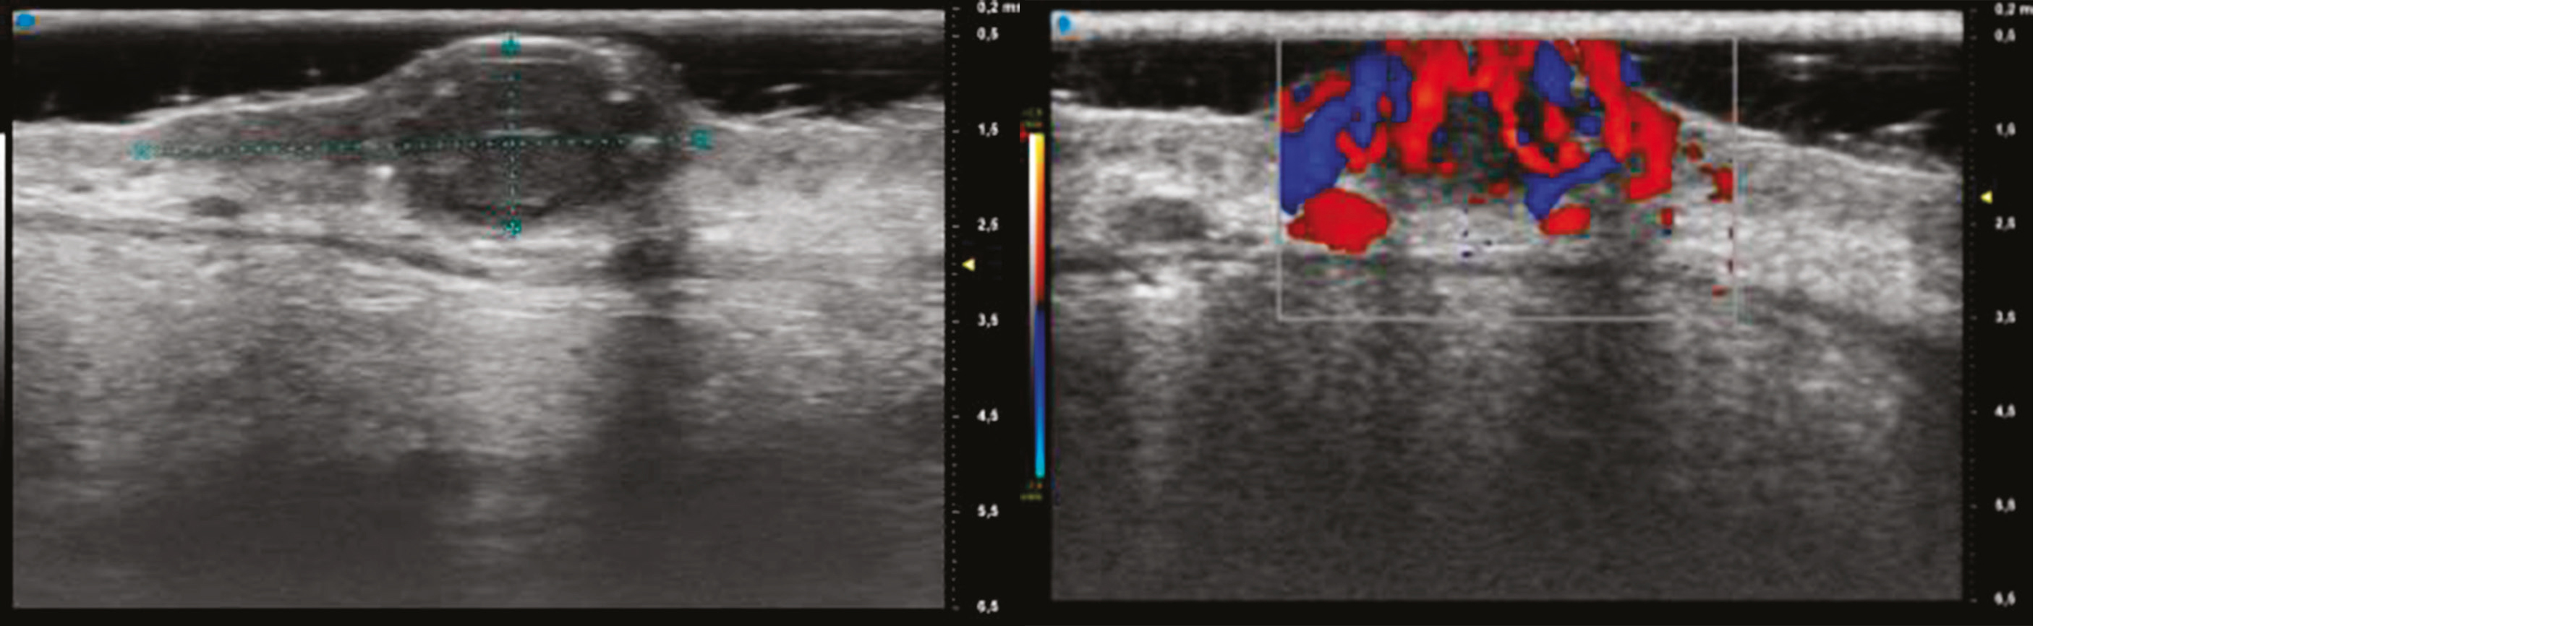

Enfin, une échographie ultra-haute fréquence (Vevo MD®) metait en évidence une lésion hypoéchogène de 1,94 mm d'épaisseur avec en mode couleur une hypervascularisation.